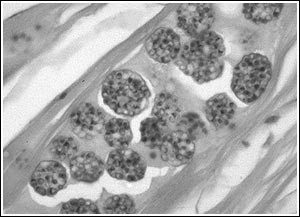

pelistophora

pelistophora-mycrosporidi